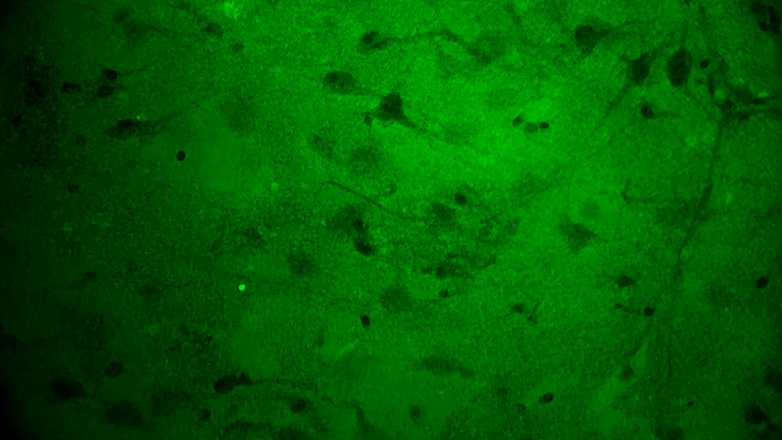

关颅期间,专家团队将其余3块瘤体组织应用EndoSCell®扫查以观察肿瘤细胞形态,无一例外,3块组织的细胞图像均符合“核异型性明显、分布密集且不规则”的肿瘤形态特征,其中一块还意外发现了清晰的神经元细胞。EndoSCell®高清直观的细胞图像给专家们留下了深刻印象,参与本次手术的张帅专家表示有合适机会或将尝试在体应用。

3.神经元细胞:神经纤维束清晰、密度低。